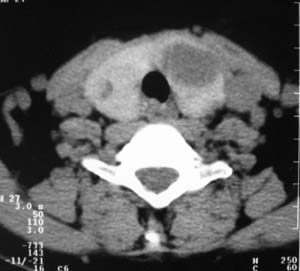

以下是引用zsl6918在2007-8-27 14:40:00的发言:[br]双侧甲状腺多发性低密度占位,边界清晰,密度欠均匀,尤以左侧明显,与周围组织分解清,考虑多发性腺瘤可能性大,不除外结节性甲状腺肿

以下是引用liaizhi在2007-8-27 15:20:00的发言:[br]双侧甲状腺散在多个囊性第密度影,左侧最大一个病灶与正常甲状腺分界尚可,气管受压稍右移。考虑甲状腺瘤的可能性大。